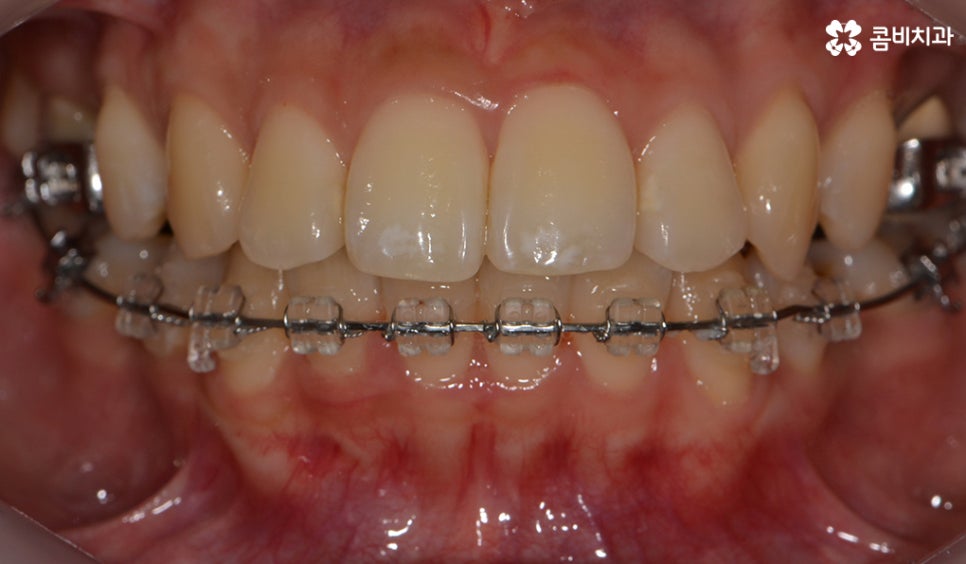

장치를 부착하고 치료의 경과 모습

콤비교정은 평상시 크게 웃지 않는 이상 외부에 시술 사실이

거의 알려지지 않을 정도로 심미성이 우수하기 때문에

직업적인 이유나 성향적으로 교정 장치에 대한 심미적 부담감으로

인해서 망설이셨던 분들에게 많이 선호되고 있는 장치입니다.

윗니가 설측으로 시술이 진행되고 있는 모습이며

발치를 한 부위 안쪽으로 치아가 이동하기 때문에

돌출입의 개선이 함께 이뤄지며 치열뿐 아니라

얼굴과 자연스럽게 어울리는 결과를 얻을 수 있습니다.